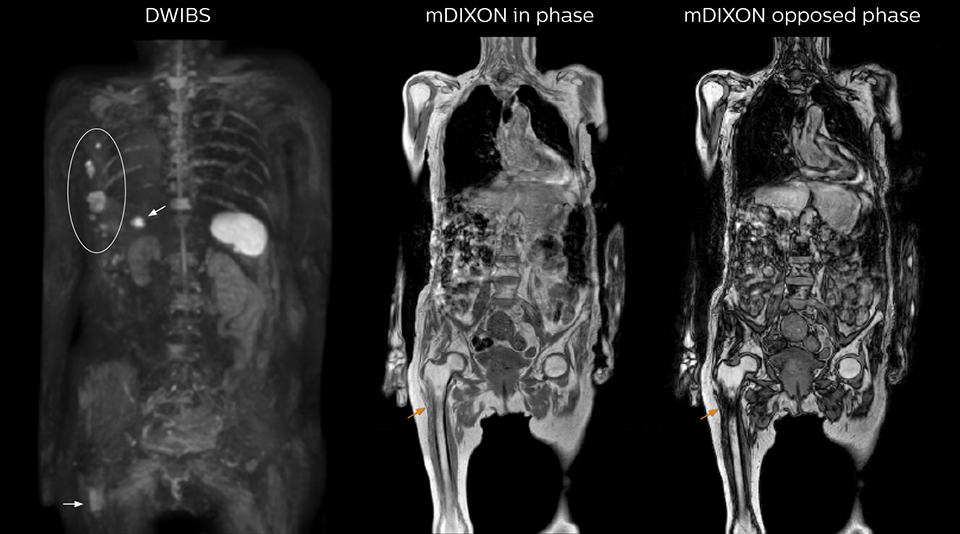

Kawasaki Sawai Hospital’s whole body protocol also includes an mDIXON FFE sequence. Because mDIXON provides images for four contrast types – water only, fat only, in-phase and out-of-phase – from a single acquisition, it is useful in many ways.

“mDIXON FFE allows us to quickly get information we need to assess the presence of fat. That gives us more information when we need to diagnose bone lesions, and when we are asked to judge fat-containing lesions such as hepatocellular or renal carcinoma,” Dr. Nobusawa says.

“The mDIXON fat images can help us to differentiate fatty bone marrow from bone lesions. This is especially useful in elderly people, who tend to have fattier bone marrow. The water images provide a high signal-to-noise ratio in the intestinal canal, which is valuable for visualizing lesions in the colon,” he says.